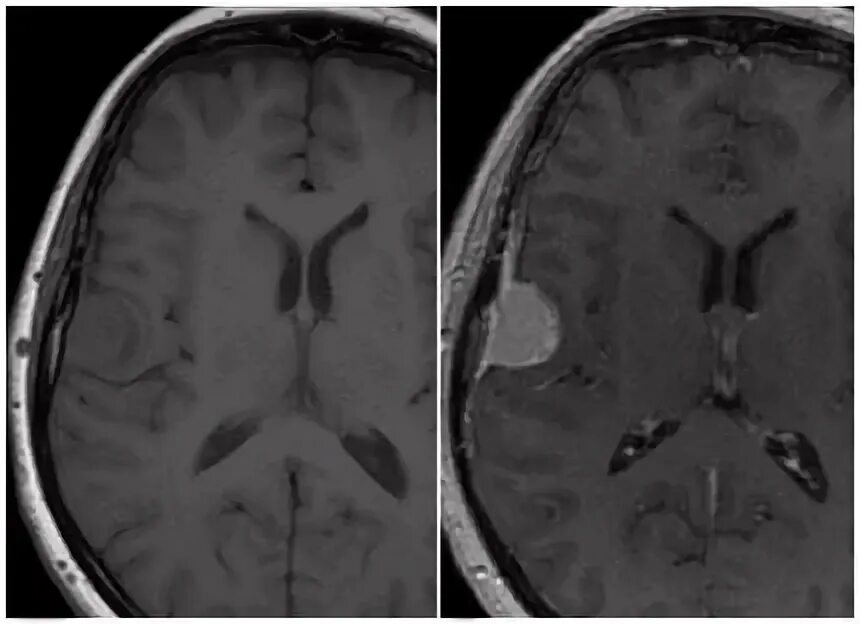

Чем отличается мрт от мрт с контрастом